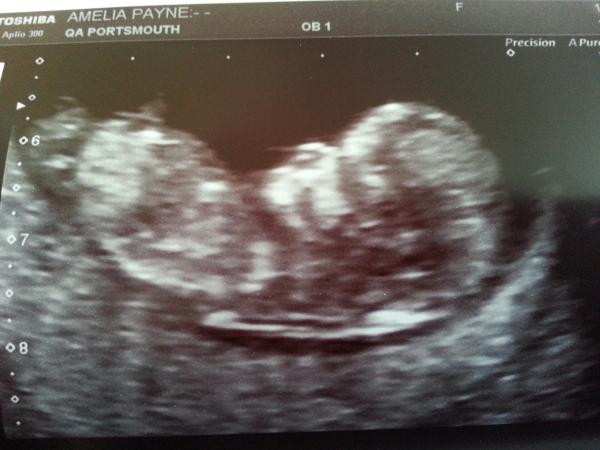

you can add photos now! Hope this works. this is my little baby!

September 2014 - where we enjoy happy scans and a healthy 2nd trimester

Yay! This is my baby - who is currently kicking me while I eat lunch!

Excited that we can upload pics, so here's my one :)

Loving the scan pics. Here's mine from 4 weeks ago!

LOVED looking at the scan pics, it's so exciting!! Hope nobody minds, here's my little bean.